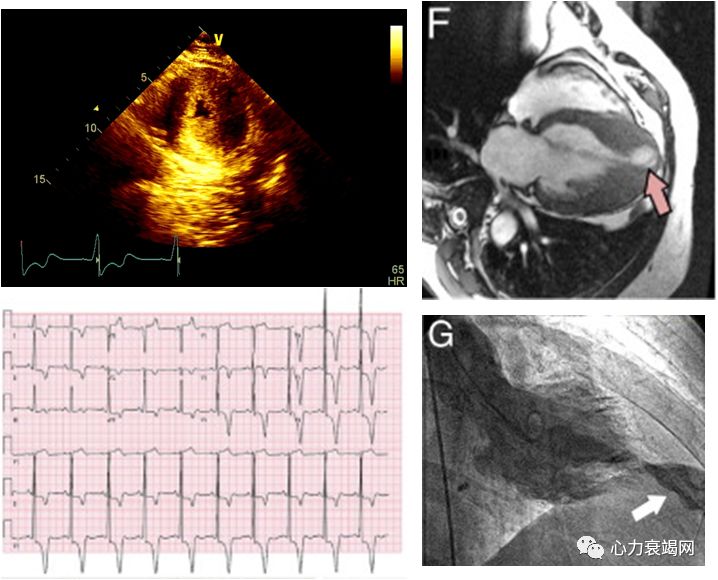

左房内径轻度增大,左室腔正常高限

左室室间隔中远段及侧壁中段室壁增厚,致左室中部梗阻(最厚约19~20mm)

左室流出道收缩期末未见明确梗阻征象,左室中部梗阻

延迟增强后心尖部可见明显透壁样强化

印象:肥厚性心肌病,左室心尖部室壁瘤形成

➤ 肥厚性梗阻型心肌病(左心室中部梗阻)

疑诊的患者完善多普勒二维超声心动图,心脏MRI,左室造影检查

怀疑冠心病时行冠脉造影